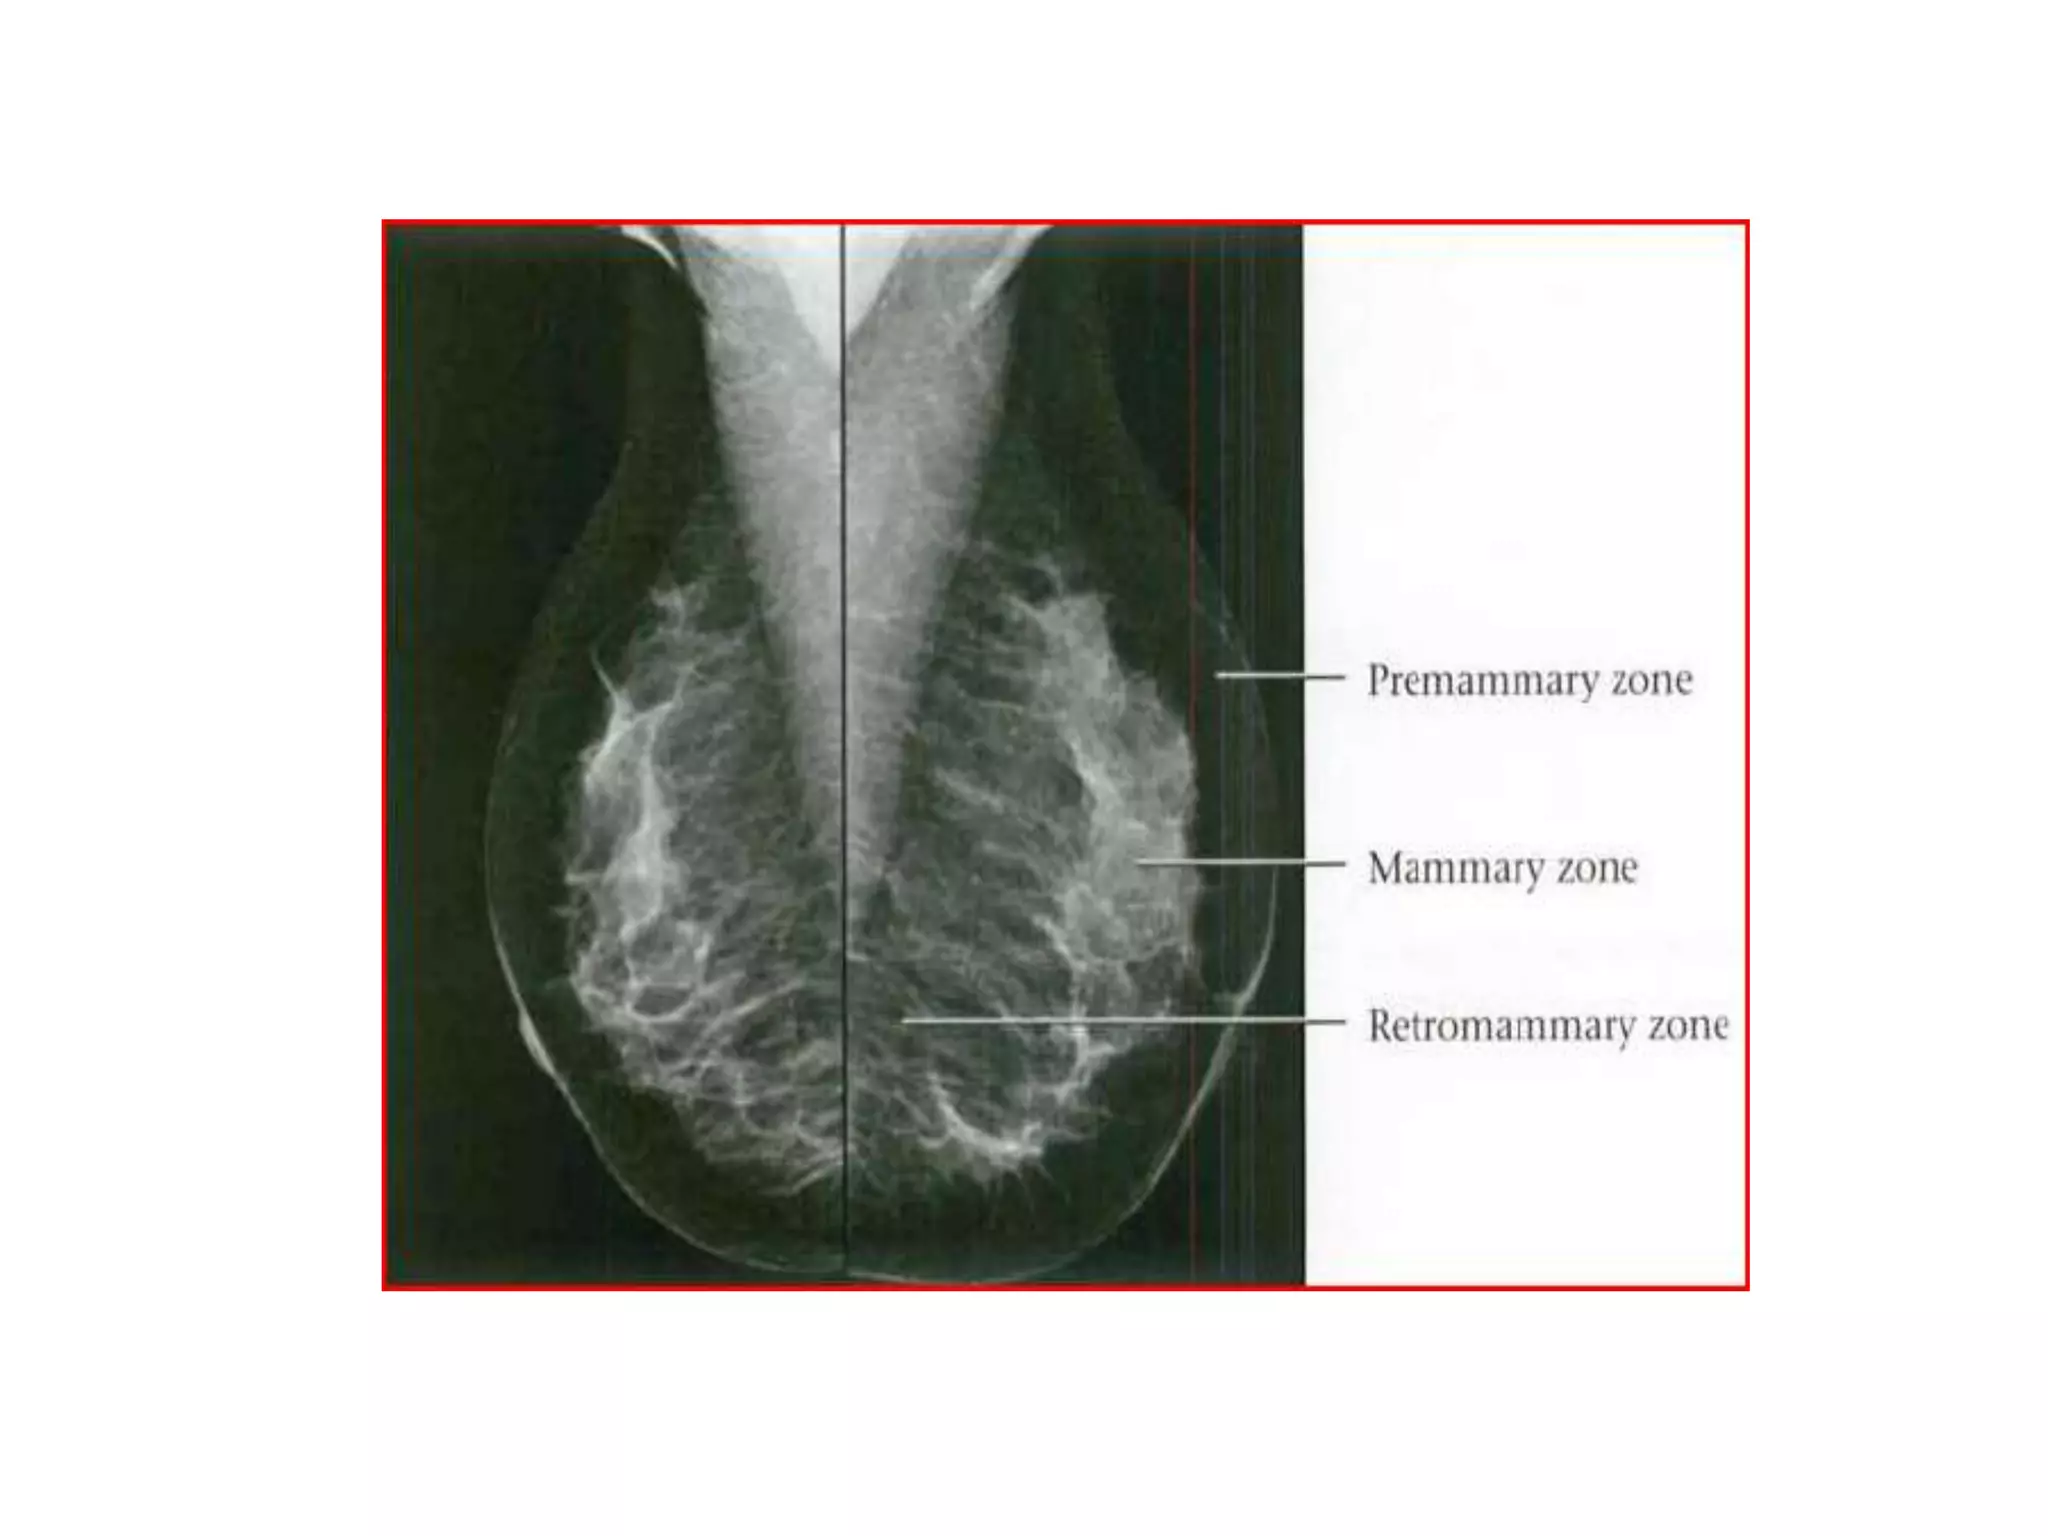

ZONAL ANATOMY

• Premammary (Subcutaneous) Zone

• Most superficial zone

• Anterior margin defined by skin, posterior margin

defined by AMF

• Contains subcutaneous fat, blood

vessels, anteriorsuspensory (Cooper) ligaments

• May contain ectopic ducts and TDLUs ASLs(Cooper

ligaments)

• Formed from two leaflets of AMF inserting into dermis

• Provide support for breast

• Usually visible on mammograms and sonograms

• Mammary Zone

• Defined anteriorly by AMF and posteriorly by PMF

• Contains majority of ducts/TDLUs, stromal fat and

stromal connective tissue

• Subdivided haphazardly by interspersed ASLs.

• Retromammary Zone

• Most posterior of three zones

• Defined anteriorly by PMF and posteriorly by chest

wall

• Contains fat and PSLs which attach PMF to chest wall